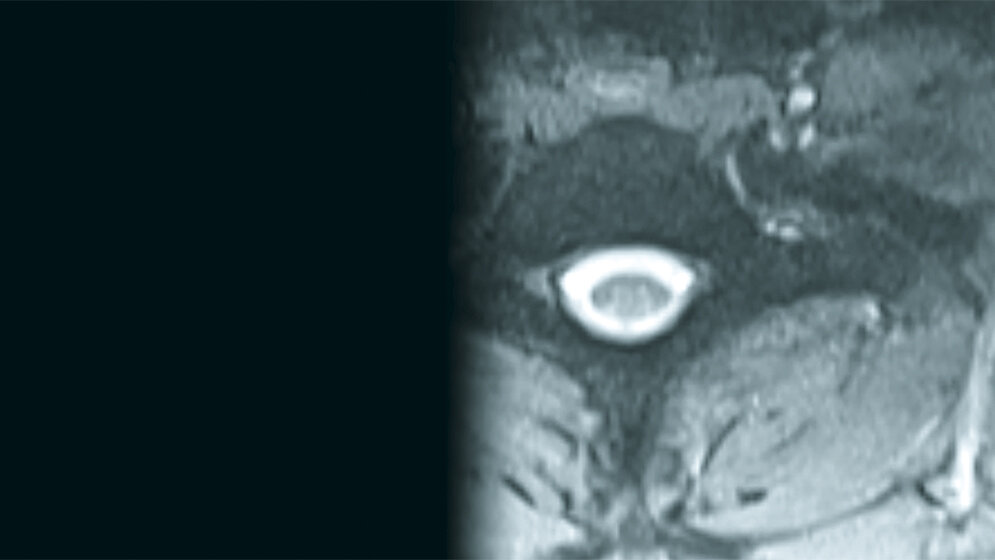

Abb. 1.1: Transversales MRT (T2 GE, 1 T): Halsrippe links bei HWK 7, im axialen MRT gut abgrenzbar © Für alle: H.-J. Thiel

Die Inzidenz der zahlenmäßig varianten Rippenanlagen beträgt 6,3 %. Bei isoliertem Vorkommen handelt es sich um Normvarianten. Zervikale Rippen kommen bei etwa 2 % der Population vor. Sie sind in der Differenzialdiagnose bei supraklavikulären Raumforderungen zu berücksichtigen.